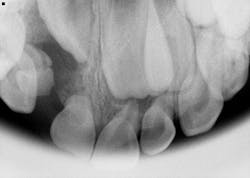

A healthy 7-year-old male presents for his new-patient exam. A radiolucency was noted in the no. 7 area on the panoramic radiograph; subsequent occlusals were referred to for a better view where the lesion appeared to focalize around the coronal portion of no. 7. Furthermore, there was an ill-defined radiopacity within the osseous tissue, under the area where primary tooth D would be located. The area was not tender to palpation nor was there any expansion noted in the vestibular area. Mom reported that the patient had trauma to the area a few years back while playing.

The most common form of pericoronal radiolucencies are dentigerous cysts (DCs).1 DCs are “caused by fluid accumulation between the enamel surface and the reduced enamel epithelium, resulting in a cyst in which the crown is located within the lumen and root(s) outside;”2 the underlying reasoning is unknown. The most common teeth affected are mandibular third molars, maxillary canines, mandibular premolars, and the maxillary canines.1,2 It is not uncommon for a DC to displace the unerupted tooth and often any adjacent teeth. Typically, DCs are painless and slow growing; however, pain will manifest if swelling and inflammation are present.

In this particular case, the patient was referred to an oral surgeon, who removed a root fragment of what was assumed to be tooth D as well as another piece of random deformed tooth structure. The cyst, along with what appeared to be tooth no. 7 (deformed), was surgically enucleated and the specimen was sent off for biopsy. Results came back as a benign dentigerous cyst. Tooth no. 8—although rotated—appeared to be unaffected.